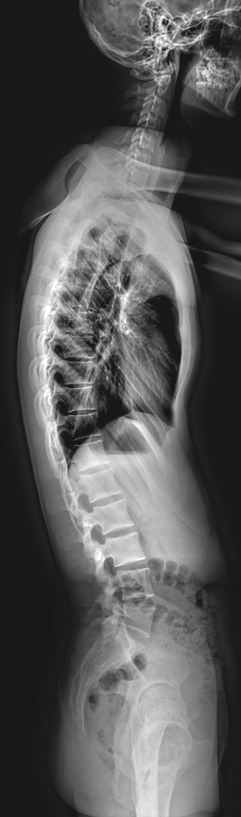

Изменения позвоночника хорошо видны на рентгене, который и назначают в качестве первичного обследования. Если симптомы говорят о поражении нескольких отделов позвоночника, а также когда необходимо выявить изменения на всей его длине, назначают стичинг. Это полный снимок всего позвоночного столба, состоящий из нескольких обычных прицельных снимков. Они «сшиты», то есть собраны цифровым способом ― на экране компьютера.

Что может показать стичинг позвоночника в боковой проекции

• Изменение физиологических лордозов и кифозов ― усиление или сглаживание;

• Деформация дуги в виде «ступеньки» ― выдвинутого позвонка,

• Изменения толщины межпозвонковых дисков;

• Склероз замыкательных пластинок  и костные разрастания тел позвонков;

• Остеопороз костной ткани позвонков;

• Переломы, вывихи, подвывихи;

• Новообразования.

Выполняется 3 снимка: шейного, грудного и пояснично-крестцового отделов, в боковой проекции. Каждый раз занять правильное положение помогает рентгенолаборант. Экспозиция одного снимка ― около 2 секунд, в это время необходимо задержать дыхание и не шевелиться.